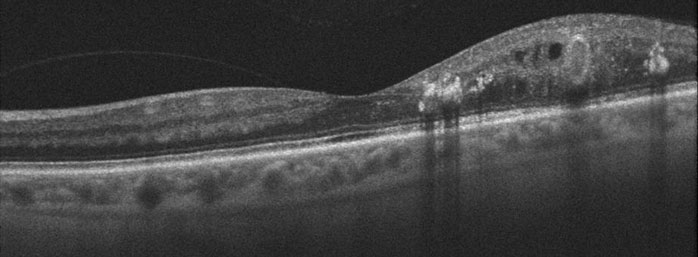

Diabetes primarily affects the blood vessels that nourish the retina. The retinal vessels work like a garden hose, bringing oxygen and other nutrients into and out of the eye. Diabetes causes them to sprout tiny leaks, or microaneurysms (non-proliferative diabetic retinopathy), which makes the surrounding retina swell and not work properly. Central vision can become blurred, just as a water droplet placed on a photograph will cause the picture to blister and become distorted (diabetic macular edema).

Diabetic macular edema